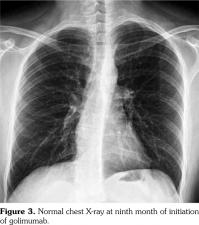

However, pain, dysfunction in daily living activities related with AS, high disease activity markers (erythrocyte sedimentation rate: 53 mm/hour, C-reactive protein: 40 mg/L [normal: 0-6 mg/L], and Bath Ankylosing Spondylitis Disease Activity Index of 6.3 [normal: 0-4]) during the period without etanercept prompted us to consider another anti-TNF-α agent. At the seventh month of etanercept cessation, golimumab with the dosage of 50 mg/month was commenced to compete with the symptoms and findings associated with AS. At the ninth month of follow-up period after inception of golimumab, the patient had no pain with normal disease activity markers. There were no pathological findings regarding sarcoidosis in the examination of the pulmonary system (Figure 3). A written informed consent was obtained from the patient.